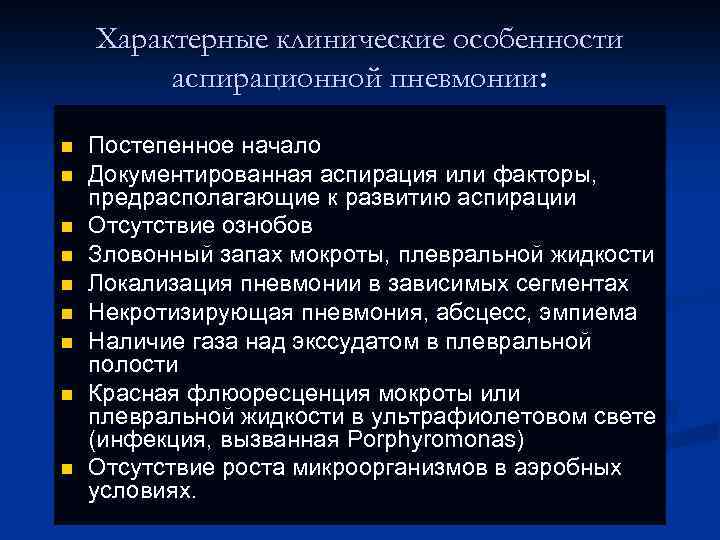

Характерные клинические особенности аспирационной пневмонии: n n n n n Постепенное начало Документированная аспирация или факторы, предрасполагающие к развитию аспирации Отсутствие ознобов Зловонный запах мокроты, плевральной жидкости Локализация пневмонии в зависимых сегментах Некротизирующая пневмония, абсцесс, эмпиема Наличие газа над экссудатом в плевральной полости Красная флюоресценция мокроты или плевральной жидкости в ультрафиолетовом свете (инфекция, вызванная Porphyromonas) Отсутствие роста микроорганизмов в аэробных условиях.